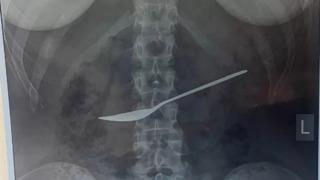

Karın ağrısı şikayetiyle hastaneye giden kızın midesinden tatlı kaşığı çıkartıldı! Doktorlar bile şaşkına döndü

Doktorlar, Rusya'da yaşayan ismi açıklanmayan bir kadın hastanın defalarca mide ağrısından şikayet etmesi ve sonunda tedaviye götürülmesi üzerine tuhaf bir keşifte bulundu. Hastanın midesinden 20 cm uzunluğunda metal bir kaşık çıkartıldı.